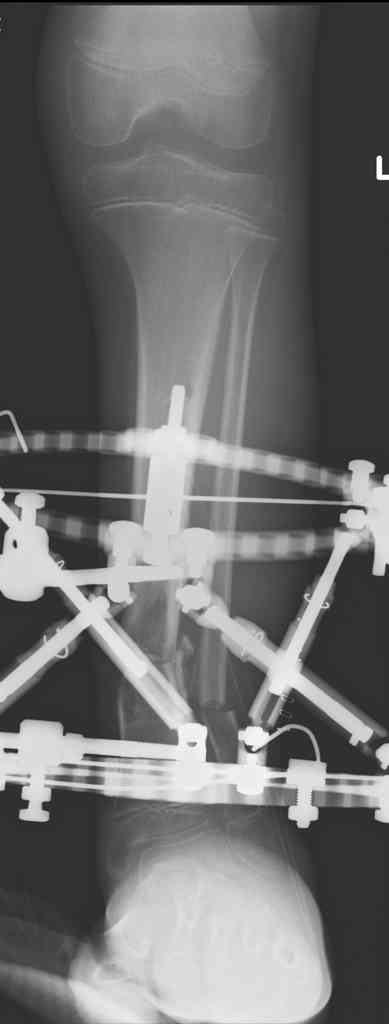

Пациент 19 лет, производственная травма, придавлен тяжелой плитой. Политравма (ISS 21).

1 - рентгенограмма (прошу прощения за качество) при поступлении;

2 - внешний вид голени;

Произведено ПХО, acute shortening (5 см), фиксация стержневым аппаратом Hoffman.

3,4 - через 4 недели наложен спице-стержневой аппарат, произведена остеотомия большеберцовой кости в верхней трети, раны зажили, проводилась дистракция в аппарате.